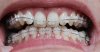

Wie versprochen ein Bild der Aufbisse im OK, auf den 7ern "innen". Dadurch sieht man sie zwar von außen nicht, die Auflieg-Fläche ist aber im Vergleich zu deinen relativ klein. Den genauen Grund/Unterschied kenn ich nicht, kauen kann ich durch den großen Abstand aber sowieso nicht. Also wird schon passen:)

spannend - Deine Aufbisse sehen ja ganz anders aus als meine. Bei mir ist ja richtig weißer Zement komplett auf der Zahnkrone und bei Dir ist es ein blaues "Türmchen". Mich würde interessieren, ob Du damit später kauen kannst. Ich kann auf meinen Aufbissen tatsächlich kauen (es fühlt sich nur sehr, sehr strange an).

das sind aber heftige Aufbisse...

Ich hatte glücklicherweise keine und bin da jetzt auch kein Experte aber mich verwundert dabei,

das sie bei der Höhe so schmal sind - das sind ja schon kleine Stalaktiten :eek:

Bei so einer Höhendifferenz hätte ich mit viel breiteren und flächigeren Ausbissen gerechnet.

"Türmchen" trifft es ganz gut. Im Moment sind sie mir zu schmal, um kauen auszuprobieren. Sie sind ja die einzige potenzielle "Kaufläche" da meine Backenzähne geschätzt 3 - 4 Millimeter voneinander entfernt sind. Mit der Zeit soll sich der tiefe Biss ja heben, dann werden sie hoffentlich kleiner.